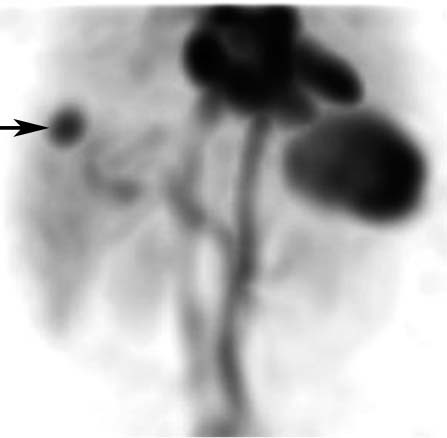

You think that the following is a hemangioma in a fatty liver, but the mid-level provider doesn’t believe you. The patient has abandoned pacer leads and can’t get an MRI. What is your next step?

Tagged RBC scan to look for hemangiomas

tagged RBC scan demonstrating hemangiomas in the liver